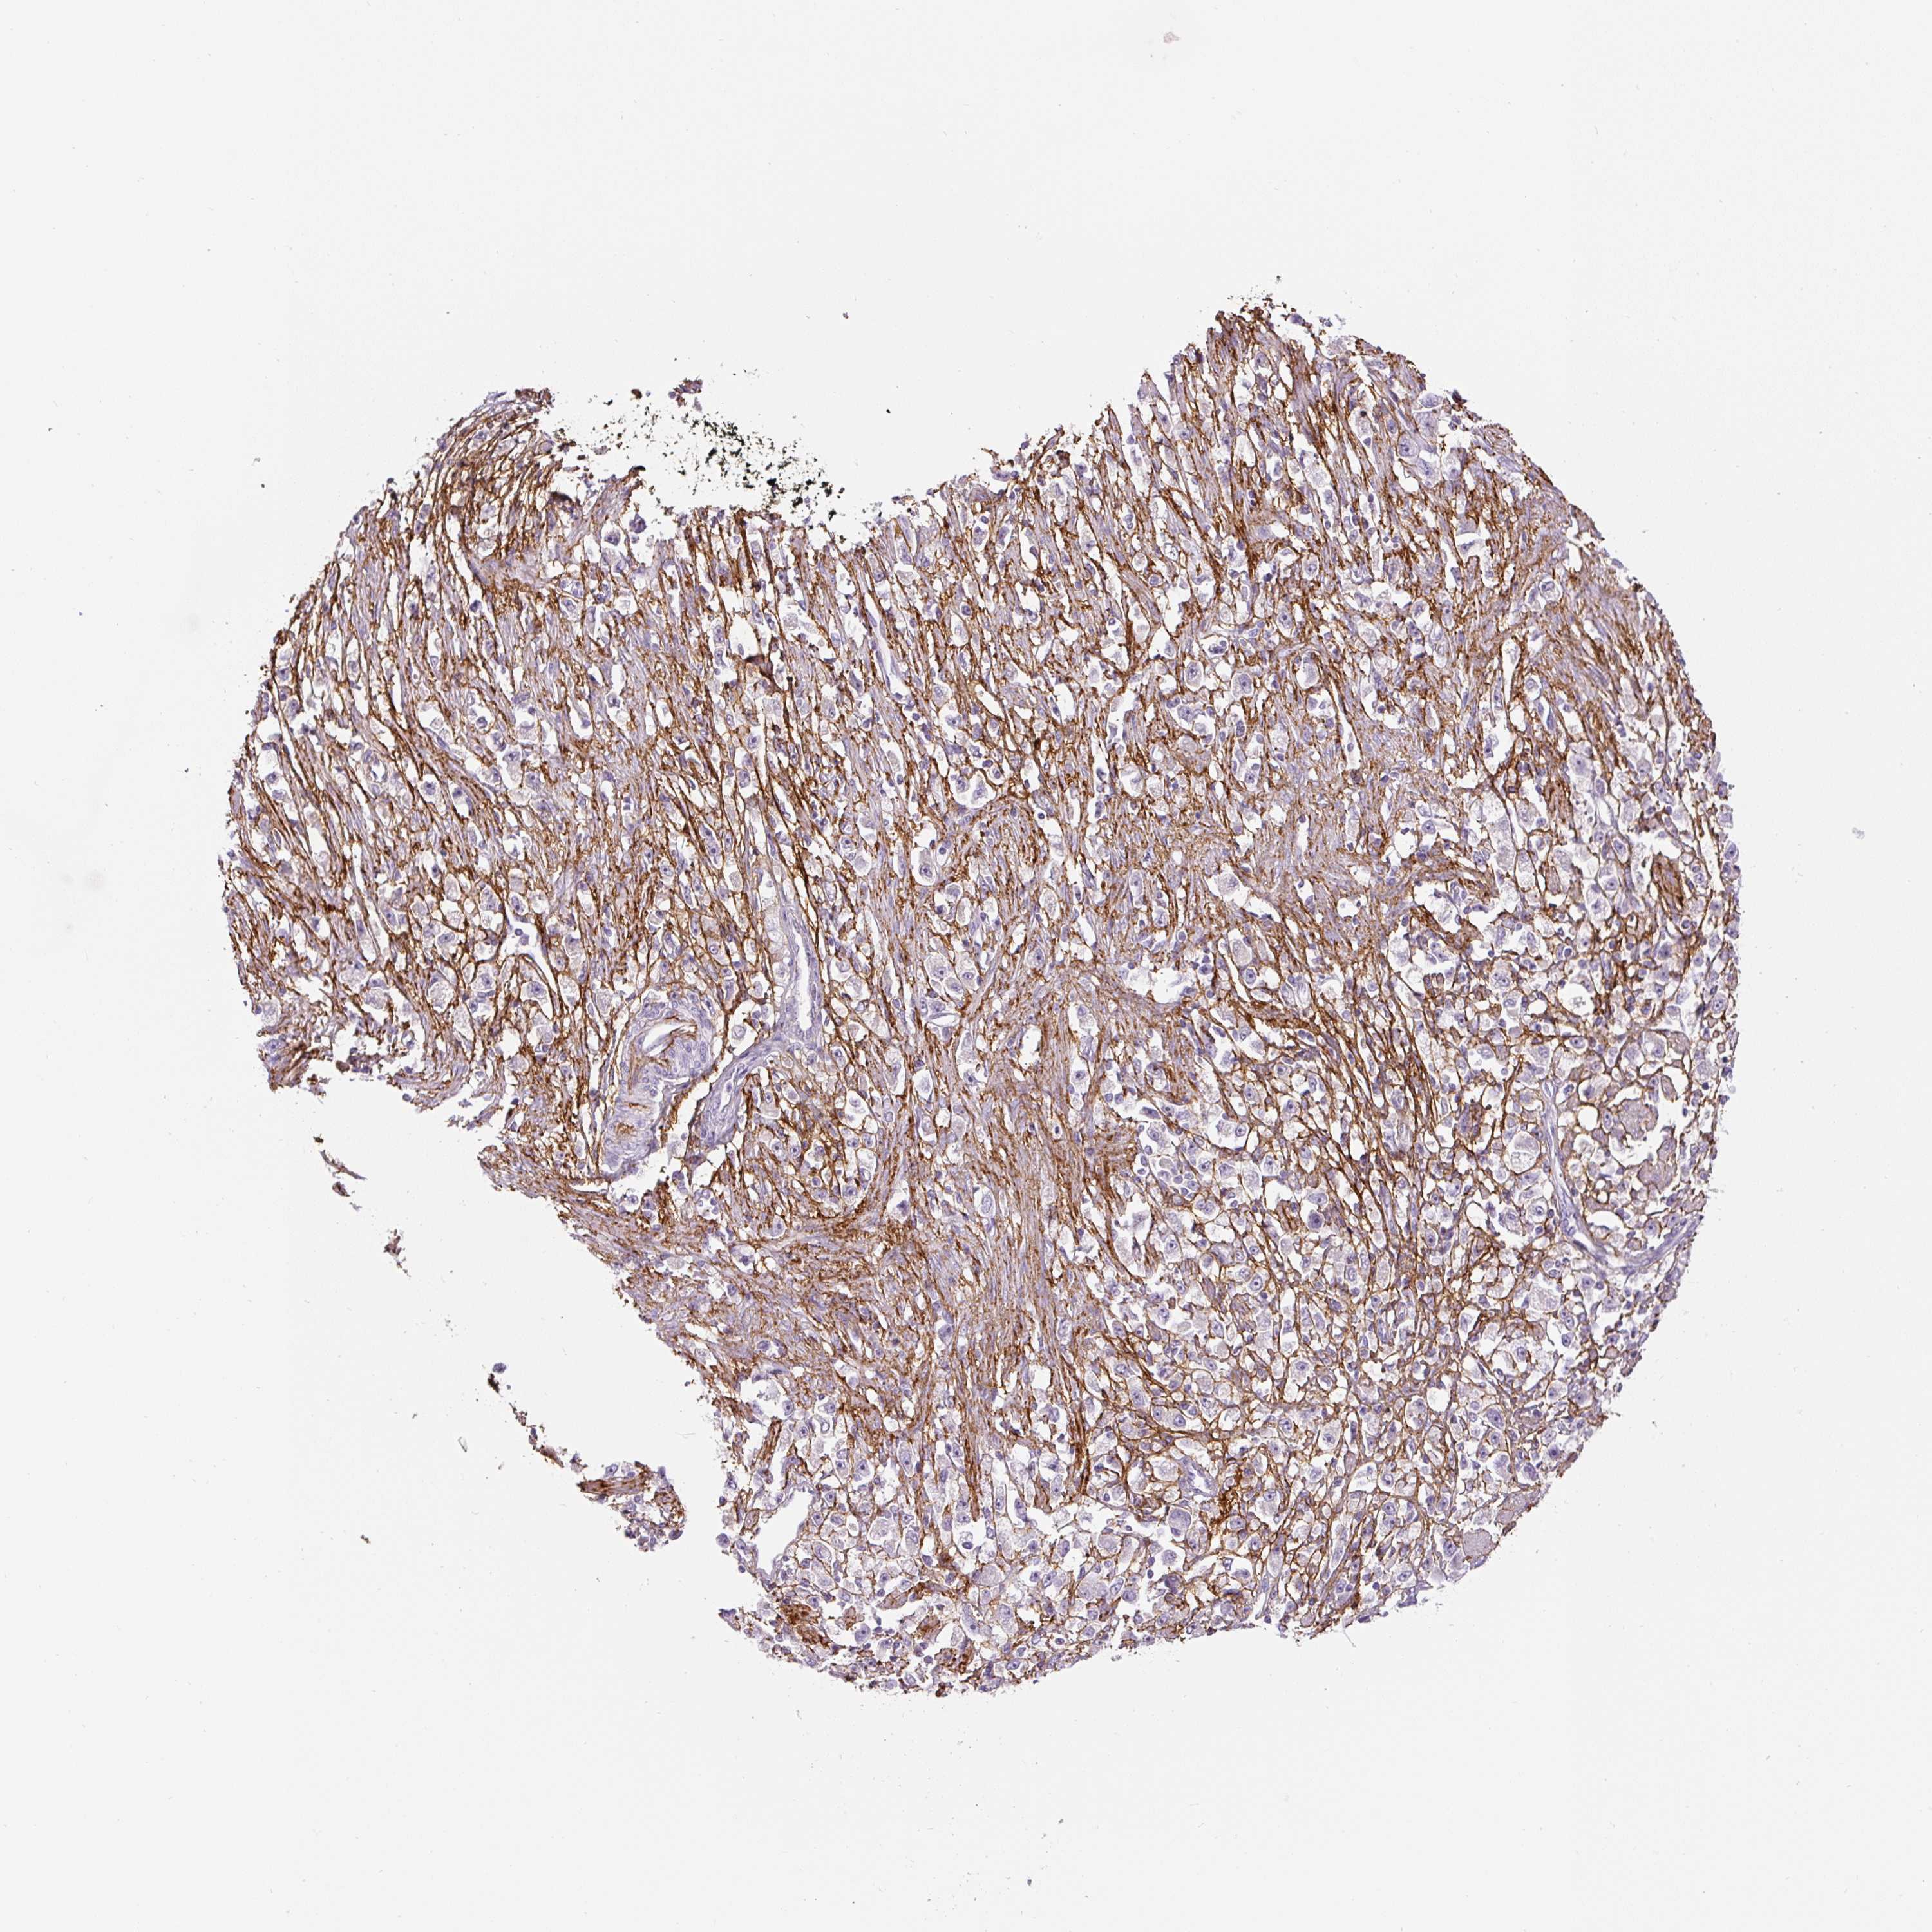

STOMACH CANCER - Protein expressioni

A mouse-over function shows sample information and annotation data. Click on an image to view it in a full screen mode. Samples can be filtered based on level of antibody staining by selecting one or several of the following categories: high, medium, low and not detected. The assay and annotation is described here.

Note that samples used for immunohistochemistry by the Human Protein Atlas do not correspond to samples in the TCGA dataset.

Antibody stainingi

Antibody staining in the annotated cell types in the current human tissue is reported as not detected, low, medium, or high, based on conventional immunohistochemistry profiling in selected tissues. This score is based on the combination of the staining intensity and fraction of stained cells.

Each image is clickable and will lead to virtual microscopy that enables deeper exploration of all samples and also displays staining intensity scores, fraction scores and subcellular localization as well as patient and tissue information for each sample.

HPA017759

HPA021057

CAB002670

CAB058696

CAB068188

CAB080202

Staining

High

Medium

Low

Not detected

Intensity

Strong

Moderate

Weak

Negative

Quantity

>75%

75%-25%

<25%

None

Location

Nuclear

Cytoplasmic/membranous

Cytoplasmic/membranous,nuclear

Adenocarcinoma, NOS

Adenocarcinoma, High grade